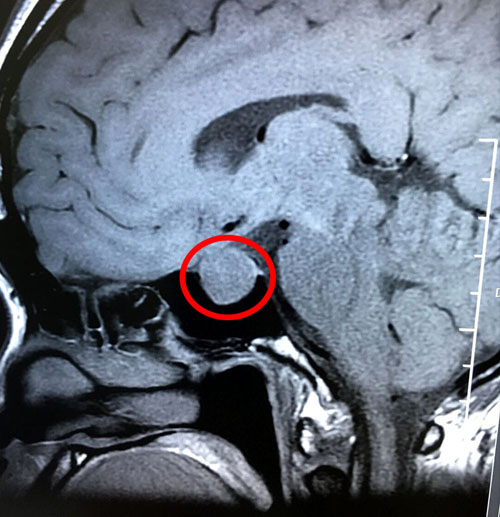

在醫(yī)院神經(jīng)外科潘仁龍主任的安排下,鄭鈺玲又做了檢查,發(fā)現(xiàn)垂體瘤又長大了,大小是1.9*1.5*1.7公分,而且超蝶鞍生長。完善血尿常規(guī),生化,凝血,心電,彩超等各項(xiàng)檢查之后,未發(fā)現(xiàn)手術(shù)禁忌。潘仁龍主任和李士其教授又進(jìn)行了會(huì)診和術(shù)前討論。

術(shù)前影像:垂體大腺瘤,超蝶鞍生長

待準(zhǔn)備就緒后,1月3日上午, 鄭鈺玲被送進(jìn)了手術(shù)室。麻醉順利后,李士其教授采用經(jīng)蝶竇微創(chuàng)手術(shù)方式,在顯微鏡下,從右側(cè)鼻腔入路,在窺鏡下找到蝶竇開口... 分塊吸除淡黃色的腫瘤組織,切除完畢后,止血復(fù)位。 整個(gè)手術(shù)不到一小時(shí)就完成,術(shù)中僅出血10毫升。術(shù)后患者被醫(yī)護(hù)人員喚醒,安全送入ICU(重癥監(jiān)護(hù)室)病房。